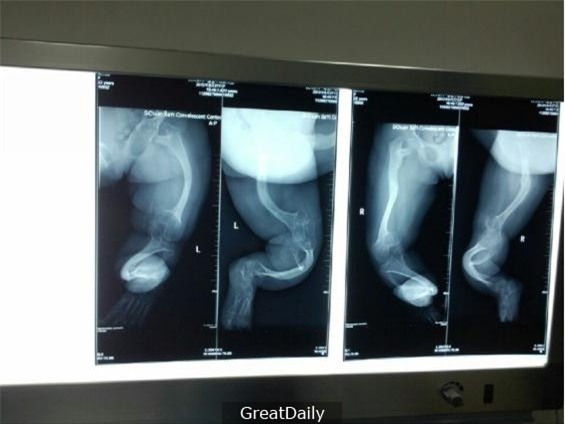

Vợ chồng cô nhanh chóng đưa con đến bệnh viện để kiểm tra. Sau khi chụp X-quang, bác sĩ cho biết xương bàn chân con chị có vấn đề, nó bị uốn cong khá nghiêm trọng. Bác sĩ rất thắc mắc vì sao lại như thế nên đã gặng hỏi người mẹ.

Qua kết quả chụp X-quang cho thấy xương bàn chân của bé có dấu hiệu bị cong.